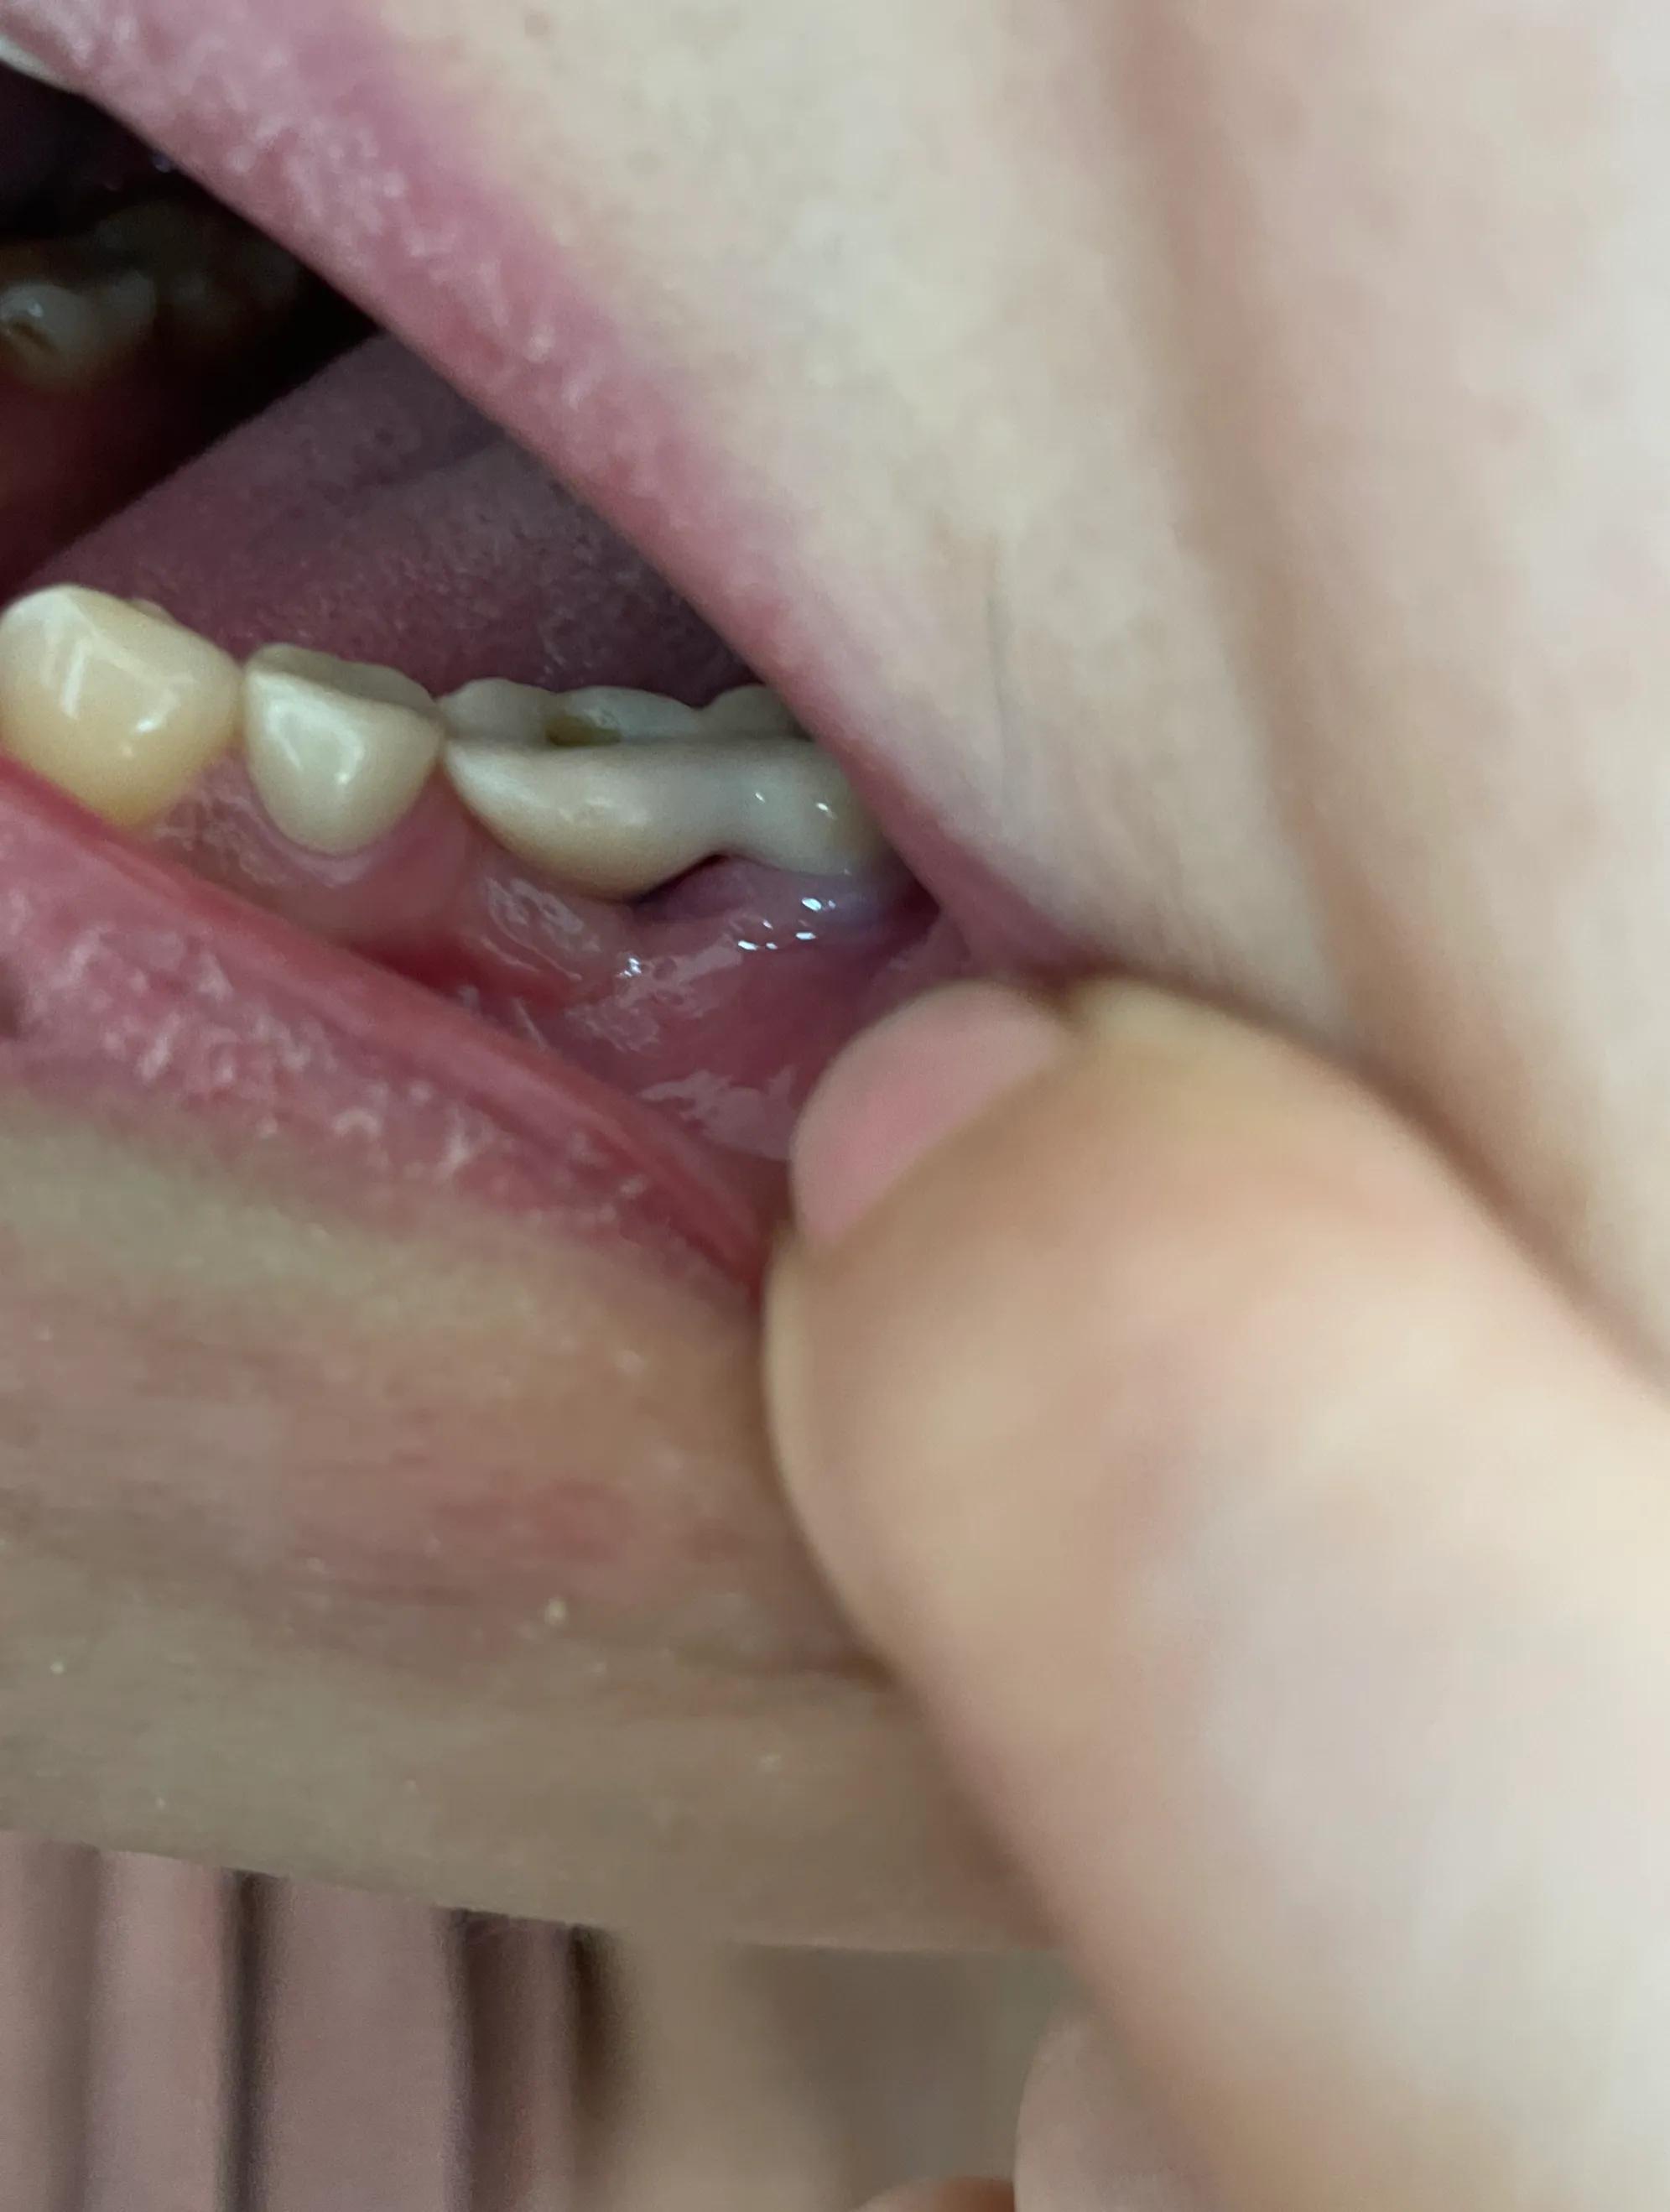

第二副牙帶好 發(fā)現(xiàn)牙齦又缺肉了 更別提貼合牙齒了 而且是一直的疼 一直難受

牙齦是外翻和牙齒分開的 顏色發(fā)白 和其他部位牙齦不是一樣顏色

我不是專業(yè)醫(yī)生 不懂他們所說的正?,F(xiàn)象都包括什么 要怎么后期維護(hù) 我現(xiàn)在先不講看不見的難受 疼 先講直觀能看見的 他們哪位醫(yī)生可以做到把大米粒塞到牙齒下面 和將近半厘米的塑料條塞過他們的牙齒 吃過東西就要用沖牙器 不然隔頓就臭了

沒辦法自己又出去拍片子 找原因 看了幾家醫(yī)院 才知道連種植體也種偏了 牙冠也沒有就位………